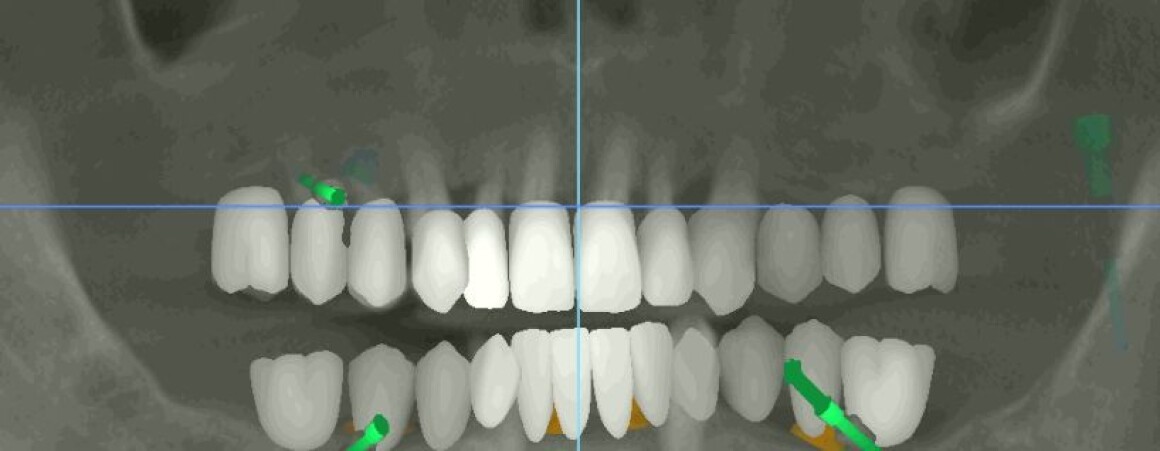

• Планирование имплантации

• Изготовление шаблонов для операции

• Имплантация 12 имплантантов за один раз